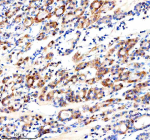

Immunohistochemical staining of Cathepsin F/CTSF using anti-CTSF antibody. Cathepsin F/CTSF was detected in a paraffin-embedded section of human stomach cancer tissue. Heat mediated antigen retrieval was performed in EDTA buffer (pH 8.0, epitope retrieval solution). The tissue section was blocked with 10% goat serum. The tissue section was then incubated with 2 ug/ml rabbit anti-CTSF antibody overnight at 4oC. Peroxidase Conjugated Goat Anti-rabbit IgG was used as secondary antibody and incubated for 30 minutes at 37oC. The tissue section was developed using an HRP secondary and DAB substrate.